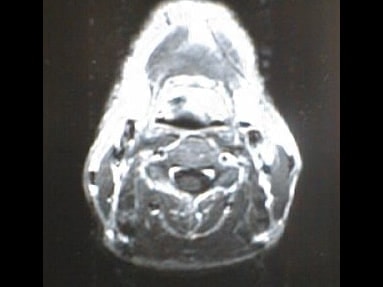

MRI画像比較

中咽頭末期がんMRI画像①

入院当時MRI画像①

中咽頭末期がん消滅時MRI画像①

入院3か月後癌消滅MRI画像①